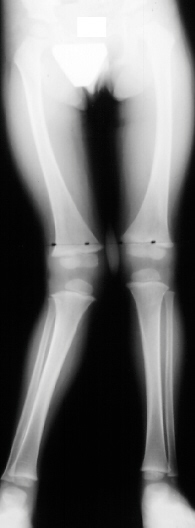

This 2 year and 9 month old male presented for evaluation

of a worsening valgus deformity of his right knee. Thirteen months

ago, his mother states the patient complained of some right leg

pain and a limp, unassociated with recognized trauma. The pain

and limp resolved over a number of weeks. Mom has noticed a progressive

cosmetic deformity of the leg without any complaints of pain or

functional limitation in running or walking. At the time of the

initial injury, the patient was examined by his doctor but there

was no history of injury and the problem was not considered to

be significant; therefore, no x-rays were performed to document

the possibility of a fracture. On physical examination moderate

to severe genu valgum of 25 degrees of the right knee and 5 degrees

of genu valgum of the left knee was noted. The right knee had

full, painless range of motion without ligamentous instability.

The left iliac crest was higher than the right. There was no significant

rotational deformity noted at the hip, knee or ankle. On gait

examination, patient was able to walk and run without tripping

or displaying a functional deficit. Standing AP films of the bilateral

lower extremities revealed a tibial femoral angle of 17 degrees

of the right knee.